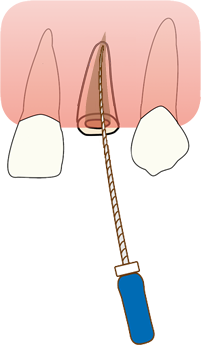

INTENTIONAL EXTRUSION 意図的挺出の現在 一般診療におけるエクストルージョンの現在 改定新版 1997年発行 送料370円 【a-4058】

エクストルージョン(歯根挺出)3 | 稲城市のランドマーク歯科クリニック,歯根だけでも抜歯にならない!エクストルージョン法(矯正的歯の廷出)症例 | 横浜市東戸塚駅より徒歩1分の歯科医院,エクストルージョン—新馬場・北品川の歯医者ならかなもり歯科クリニック|品川区|大田区,エクストルージョン(歯根挺出術)|徳島 米沢歯科クリニック|インプラント・審美・セラミック|歯科医院 歯医者,歯根だけでも抜歯にならない!エクストルージョン法(矯正的歯の廷出)症例 | 横浜市東戸塚駅より徒歩1分の歯科医院